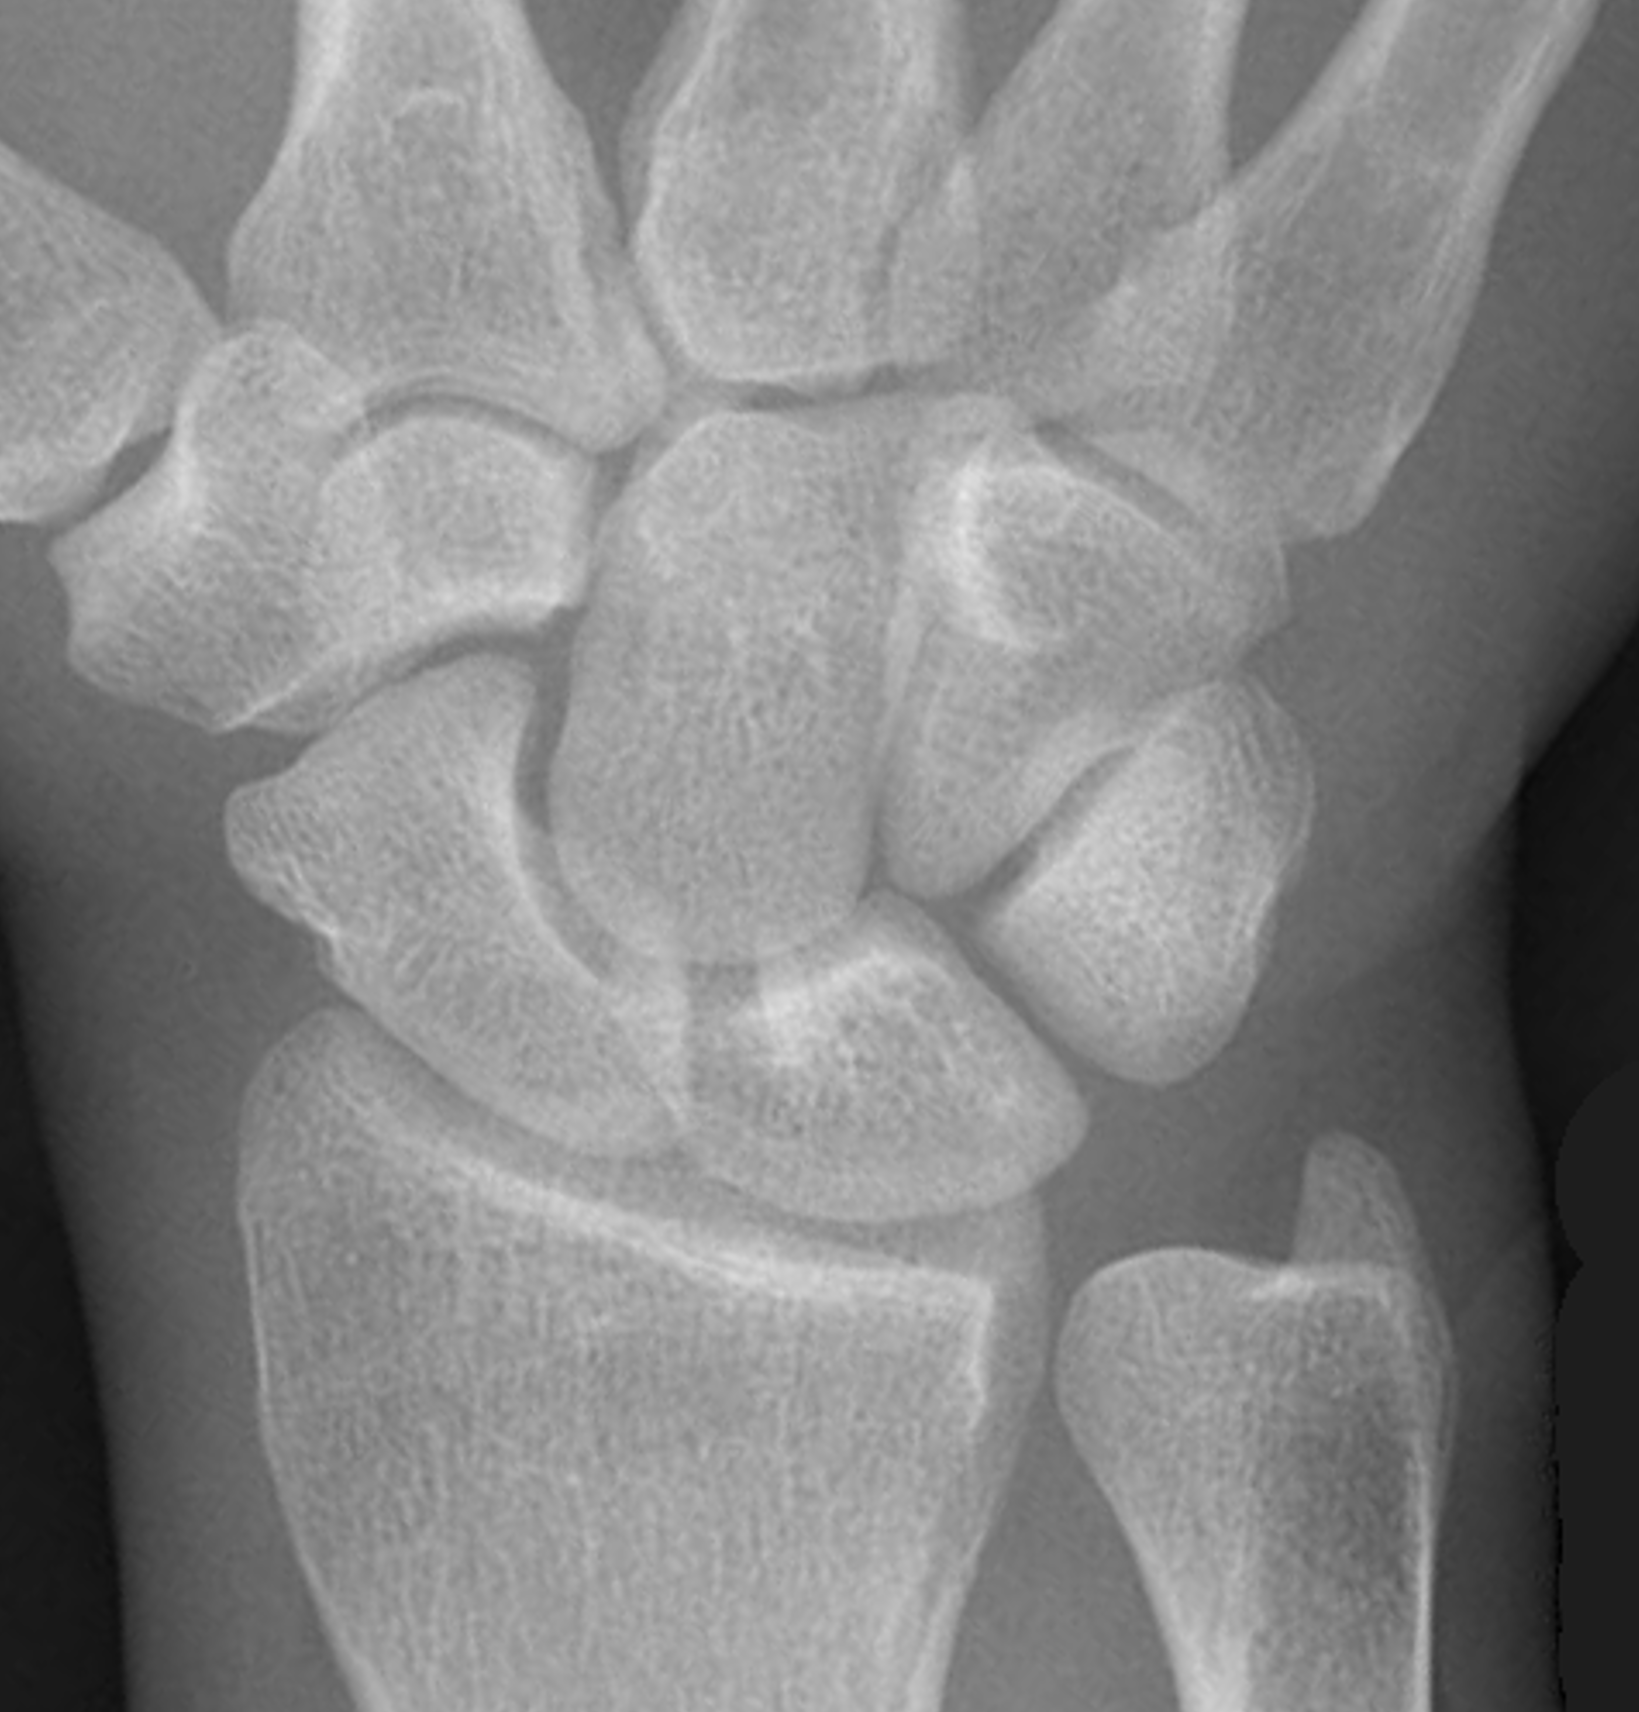

Gilula carpal arcs

Normally there are 3 smooth carpal arcs on PA xray

Arc I: Proximal cortical margins of proximal carpal row Arc II: Distal carpal margin of the proximal carpal row Arc III: Proximal cortices of the capitate and hamate |

AP X-ray

Disruption of Gilula's 3 smooth carpal arcs / triangular lunate

Normal versus disruputed Gilula's carpal arcs

Piece of pie / triangular appearance of lunate